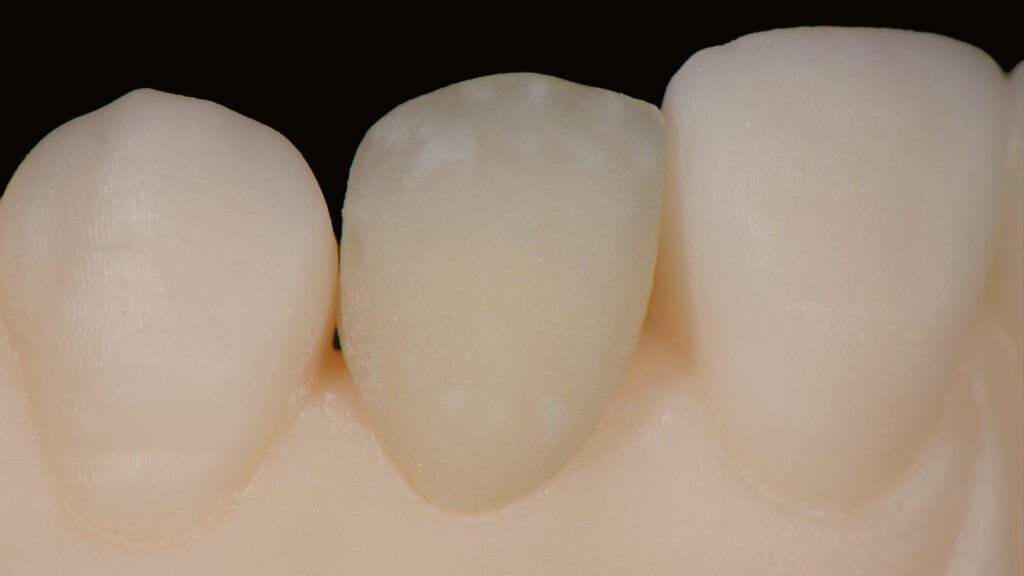

Die Gestaltung des marginalen Randes („Präparationsrand”) im bukkalen Bereich erfolgt in Absprache mit dem Zahnarzt ca. 0,2 mm subgingival (Abb. 52). Palatinal endet die Verblendkeramik supragingival, um hier die biologischen Vorteile des Zirkonoxids zu nutzen (Weichgewebekonditionierung) (Abb. 53). Vor allem im Frontzahnbereich wird das individualisierte Emergenzprofil als wichtiger Faktor für die Rekonstruktion einer zufriedenstellenden Ästhetik angesehen. Zudem werden im Frontzahnbereich mit Zirkonoxid biologisch und ästhetisch bessere Ergebnisse erzielt als mit Titan, das bei dünnem Gingiva-Biotyp durchscheinen kann (Abb. 54 und 55).

Die individuelle Formgebung der ASC-Implantatkronen ermöglicht einen reizfreien Schleimhautkontakt mit Titanadapter und konischer Innenverbindung zum Implantat (Abb. 56 und 57). Die keramische Verblendung des Zirkonoxid-Abutments erfolgt analog und ebenso detailgetreu wie beim keramischen Veneer und mit der gleichen Verblendkeramik (Lumex AC). Nach der Verblendung wird die Implantatkrone auf dem Meistermodell verschraubt und eine letzte Kontrolle der Kontaktflächen (Abb. 58 und 59), der Artikulation, der seitlichen Bewegungen und der Eckzahnführung durchgeführt. Abbildung 60 zeigt den nahtlosen Übergang der Implantatkrone zur natürlichen Gingiva. Eine Überkonturierung könnte zu einer apikalen Verschiebung führen. Eine polar_eyes-Aufnahme macht das Innere der Krone und die Details besser sichtbar (Abb. 61).

Ergebnis ist eine ästhetisch hochwertig verblendete Implantatkrone auf einem individuellen Zirkonoxidgerüst mit Titanadapter. Die mesiale Ansicht zeigt das Emergenzprofil und eine vertikale Achsneigung, die quasi von inzisal zur Implantatmitte verläuft. Der subgingivale Anteil tritt schlank aus dem Implantat aus und unterstützt mit einem konvexen Übergang zur Implantatkrone das Niveau der Gingiva (Abb. 62). Die Abutmentbasis aus Titan sorgt für eine präzise Passung, die gut kontrollierbar ist. Abbildung 63 zeigt die verschiedenen Komponenten der Implantatrestauration: Titanadapter, eine Omnigrip-Schraube und Omnigrip-Schraubendreher sowie die Vollkeramikkrone.

Eingliederung der Implantatkrone

Nach einigen Monaten war das periimplantäre Weichgewebe endgültig stabilisiert. Es zeigte sich noch eine leichte Narbenbildung am Gingivazenit. Nach vorsichtigem Ausdrehen der provisorischen TempShell-Krone offenbart sich eine gut ausgebildete Weichgewebsarchitektur. Die Gewebedicke an der Implantationsstelle ist vergleichbar mit der Situation am zu kopierenden linken lateralen Schneidezahn (Abb. 64). Die Zirkonoxidkrone mit Titanadapter wird definitiv mit dem Implantat verschraubt. Durch die detaillierte digitale Vorbereitung sind oft nur kleine Korrekturen notwendig. Meist können die Restaurationen ohne Einprobe eingegliedert werden. Die biokompatiblen Anteile der Implantatkrone (Titanadapter) und die subgingivalen Anteile der Implantatkrone gewährleisten eine optimale Anlagerung der Gingiva (Abb. 65). Der spaltfreie Sitz der Versorgung auf dem Implantat wird röntgenologisch kontrolliert.